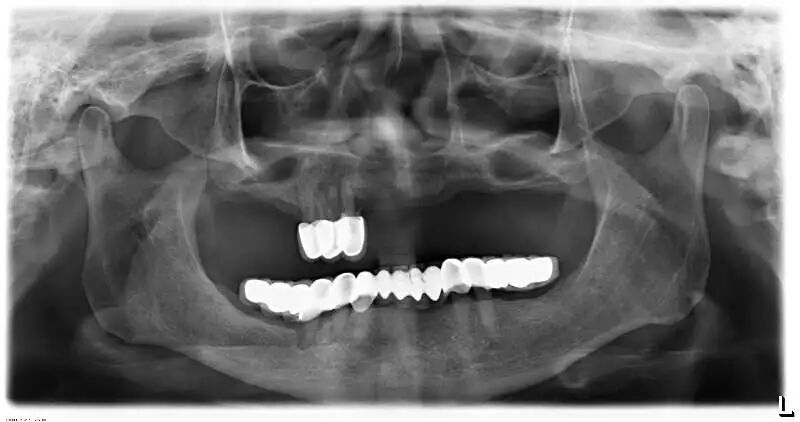

另外,烤瓷桥中的极品——“长江大桥”现象,则是普遍存在于中国各城市各基层牙科的不规范现象,与普通烤瓷桥不同,其本质是一种违反口腔生物力学原理的设计,其最常见的转归是全口牙报废,临床上很多先在基层做,两三年后去医院拆,对口腔健康的影响令人咂舌。

这样的病例实在太多,公立医院和部分高端民营口腔机构每年都要拆除很多例,后续治疗则费时费事费钱费脑筋,而且此类患者来源于社会各阶层,我见过的病例包括一些同事医生(非牙医)的父母,医生的健康意识不代表其家人,而你无法想象其中一例是拥有几百亿资产的企业家,医疗信息不对称应该是主要因素。